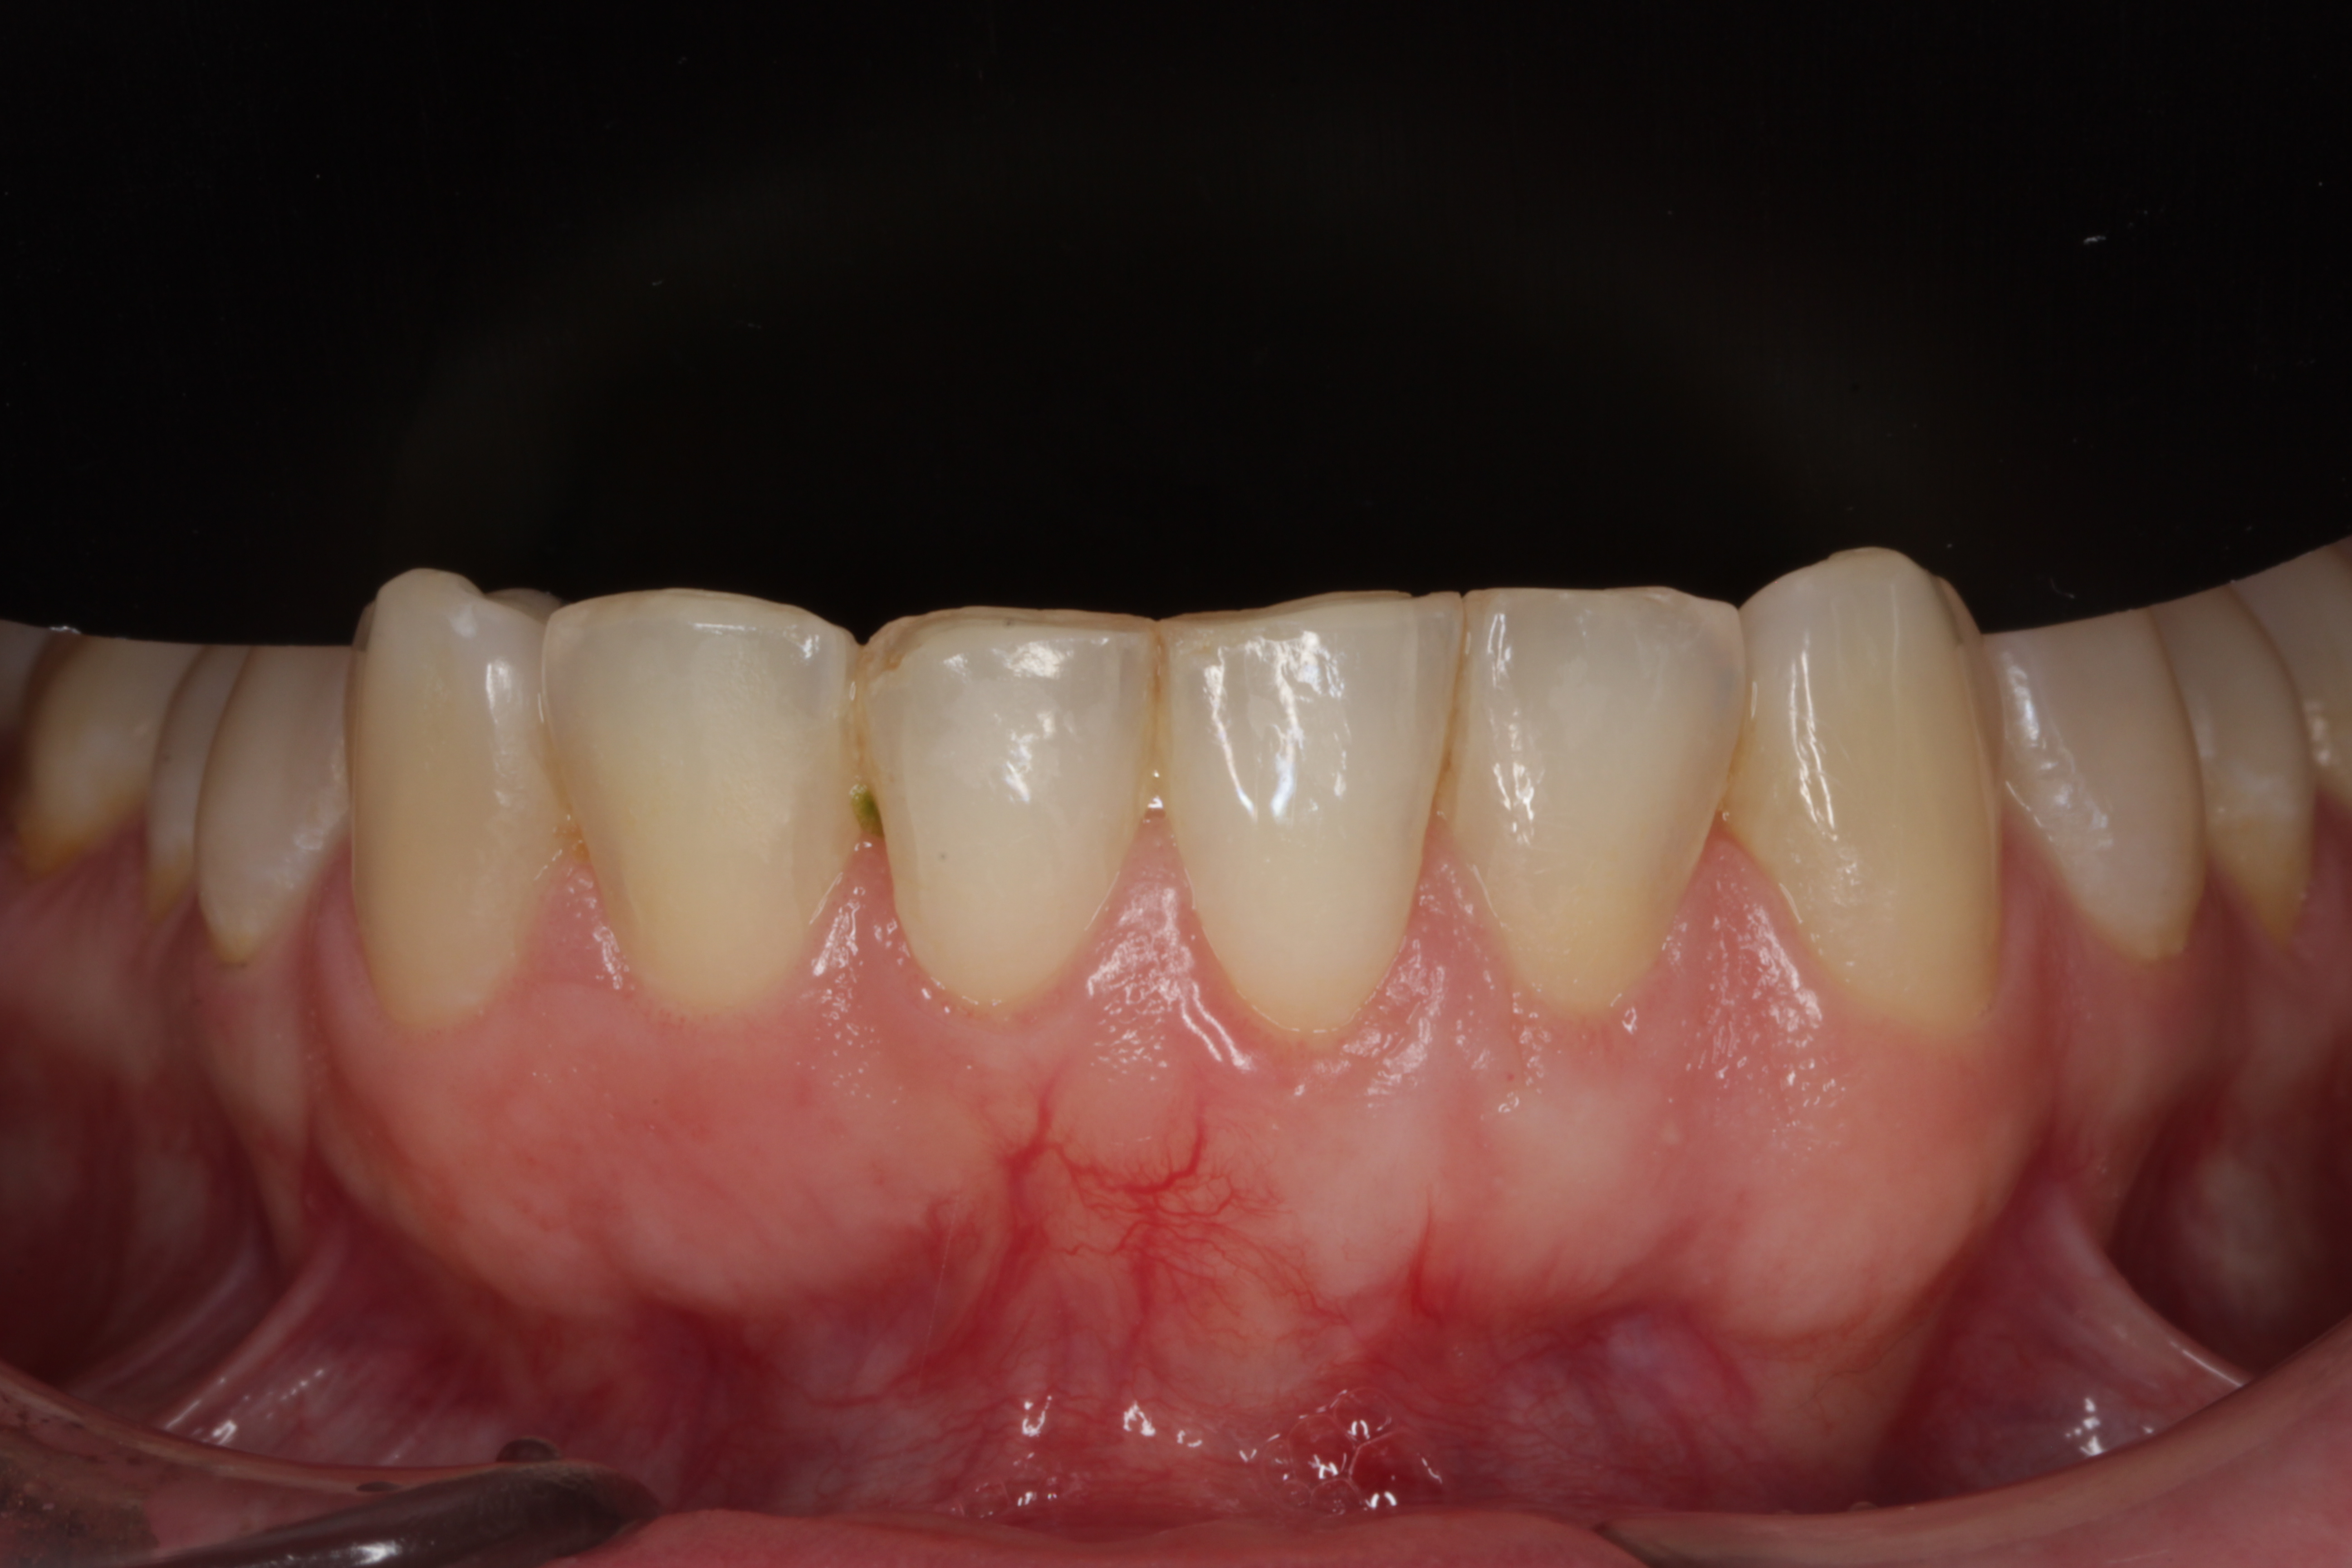

Recessie is het proces waarbij het tandvlees zich terugtrekt van het tandoppervlak, waardoor de tandwortel (deels) bloot komt te liggen. Dit resulteert in blootliggende tandhalzen. Omdat tandwortels niet bedekt zijn met hard glazuur zoals de tandkroon, zijn ze veel gevoeliger voor externe prikkels zoals temperatuurverschillen, aanraking en zuren. Bovendien zijn ze vatbaarder voor slijtage en wortelcariës (gaatjes in de wortel).

Gevolgen en Symptomen van Recessie

De meest voorkomende klachten bij teruggetrokken tandvlees zijn:

- Gevoelige tanden/tandhalzen: Pijn of een scherpe pijnscheut bij koud, warm, zoet, zuur of aanraking.

- Esthetische bezwaren: Tanden lijken langer, wat als ontsierend kan worden ervaren. Soms ontstaan donkere randjes of kiertjes.

- Verhoogd risico op wortelcariës: Blootliggende wortels zijn kwetsbaarder voor gaatjes.

- Slijtage van de tandwortel (poetsdefecten).